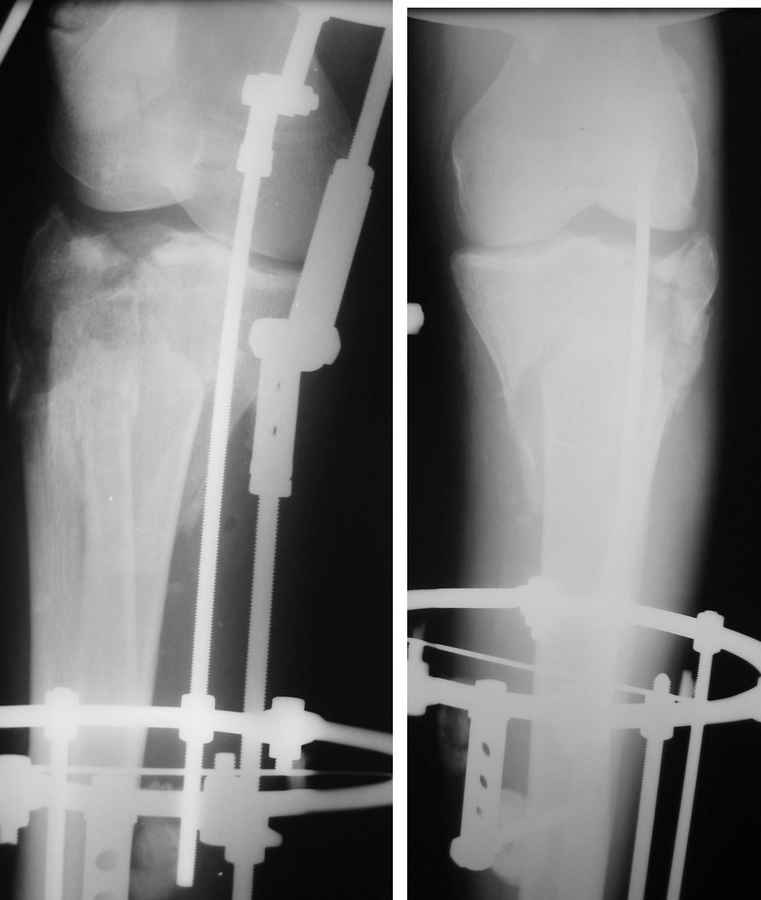

Саша, а в чем конкретно неясность? Надо полагать, вопрос не про общие принципы лечения переломов типа Schatzker VI или C3 по классификации AO, которые можно найти в любом руководстве?

Очаг некроза 4 на 5 см по передней поверхности голени не оставил никакого варианта кроме внешнего остеосинтеза.

Но решили делать в 2 этапа. Первый - восстановить ось и дать костной крошке в проксимальном отделе консолидироваться.

Второй - собственно артродез.

Но по результатам первого этапа думаем дать пациенту попользоваться ногой. А там посмотрим.

Для первого этапа достаточно. Через 5-10 дней мы бы приступили к следующему этапу. А именно, фиксация из ограниченного заднемедиального доступа 1\3 трубчатой или рекон пластиной медиального фрагмента, и остеосинтез наружного мыщелка из второго тоже ограниченного латерального доступа без артротомии, под контролем ЭОПа..... Сухой некроз в данном случае не являлся бы серьезной помехой для внутренней фиксации (во всяком случае, судя по имеющимся фото)

P.S. безусловно, с двумя пластинами LCP, каннюлироваными винтами, хроносом все это дорого... Но того же анатомического и функционального результата можно достичь, используя вместо пластин аппарат Илизарова, и разрезы для репозиции тогда нудны совсем маленькие .